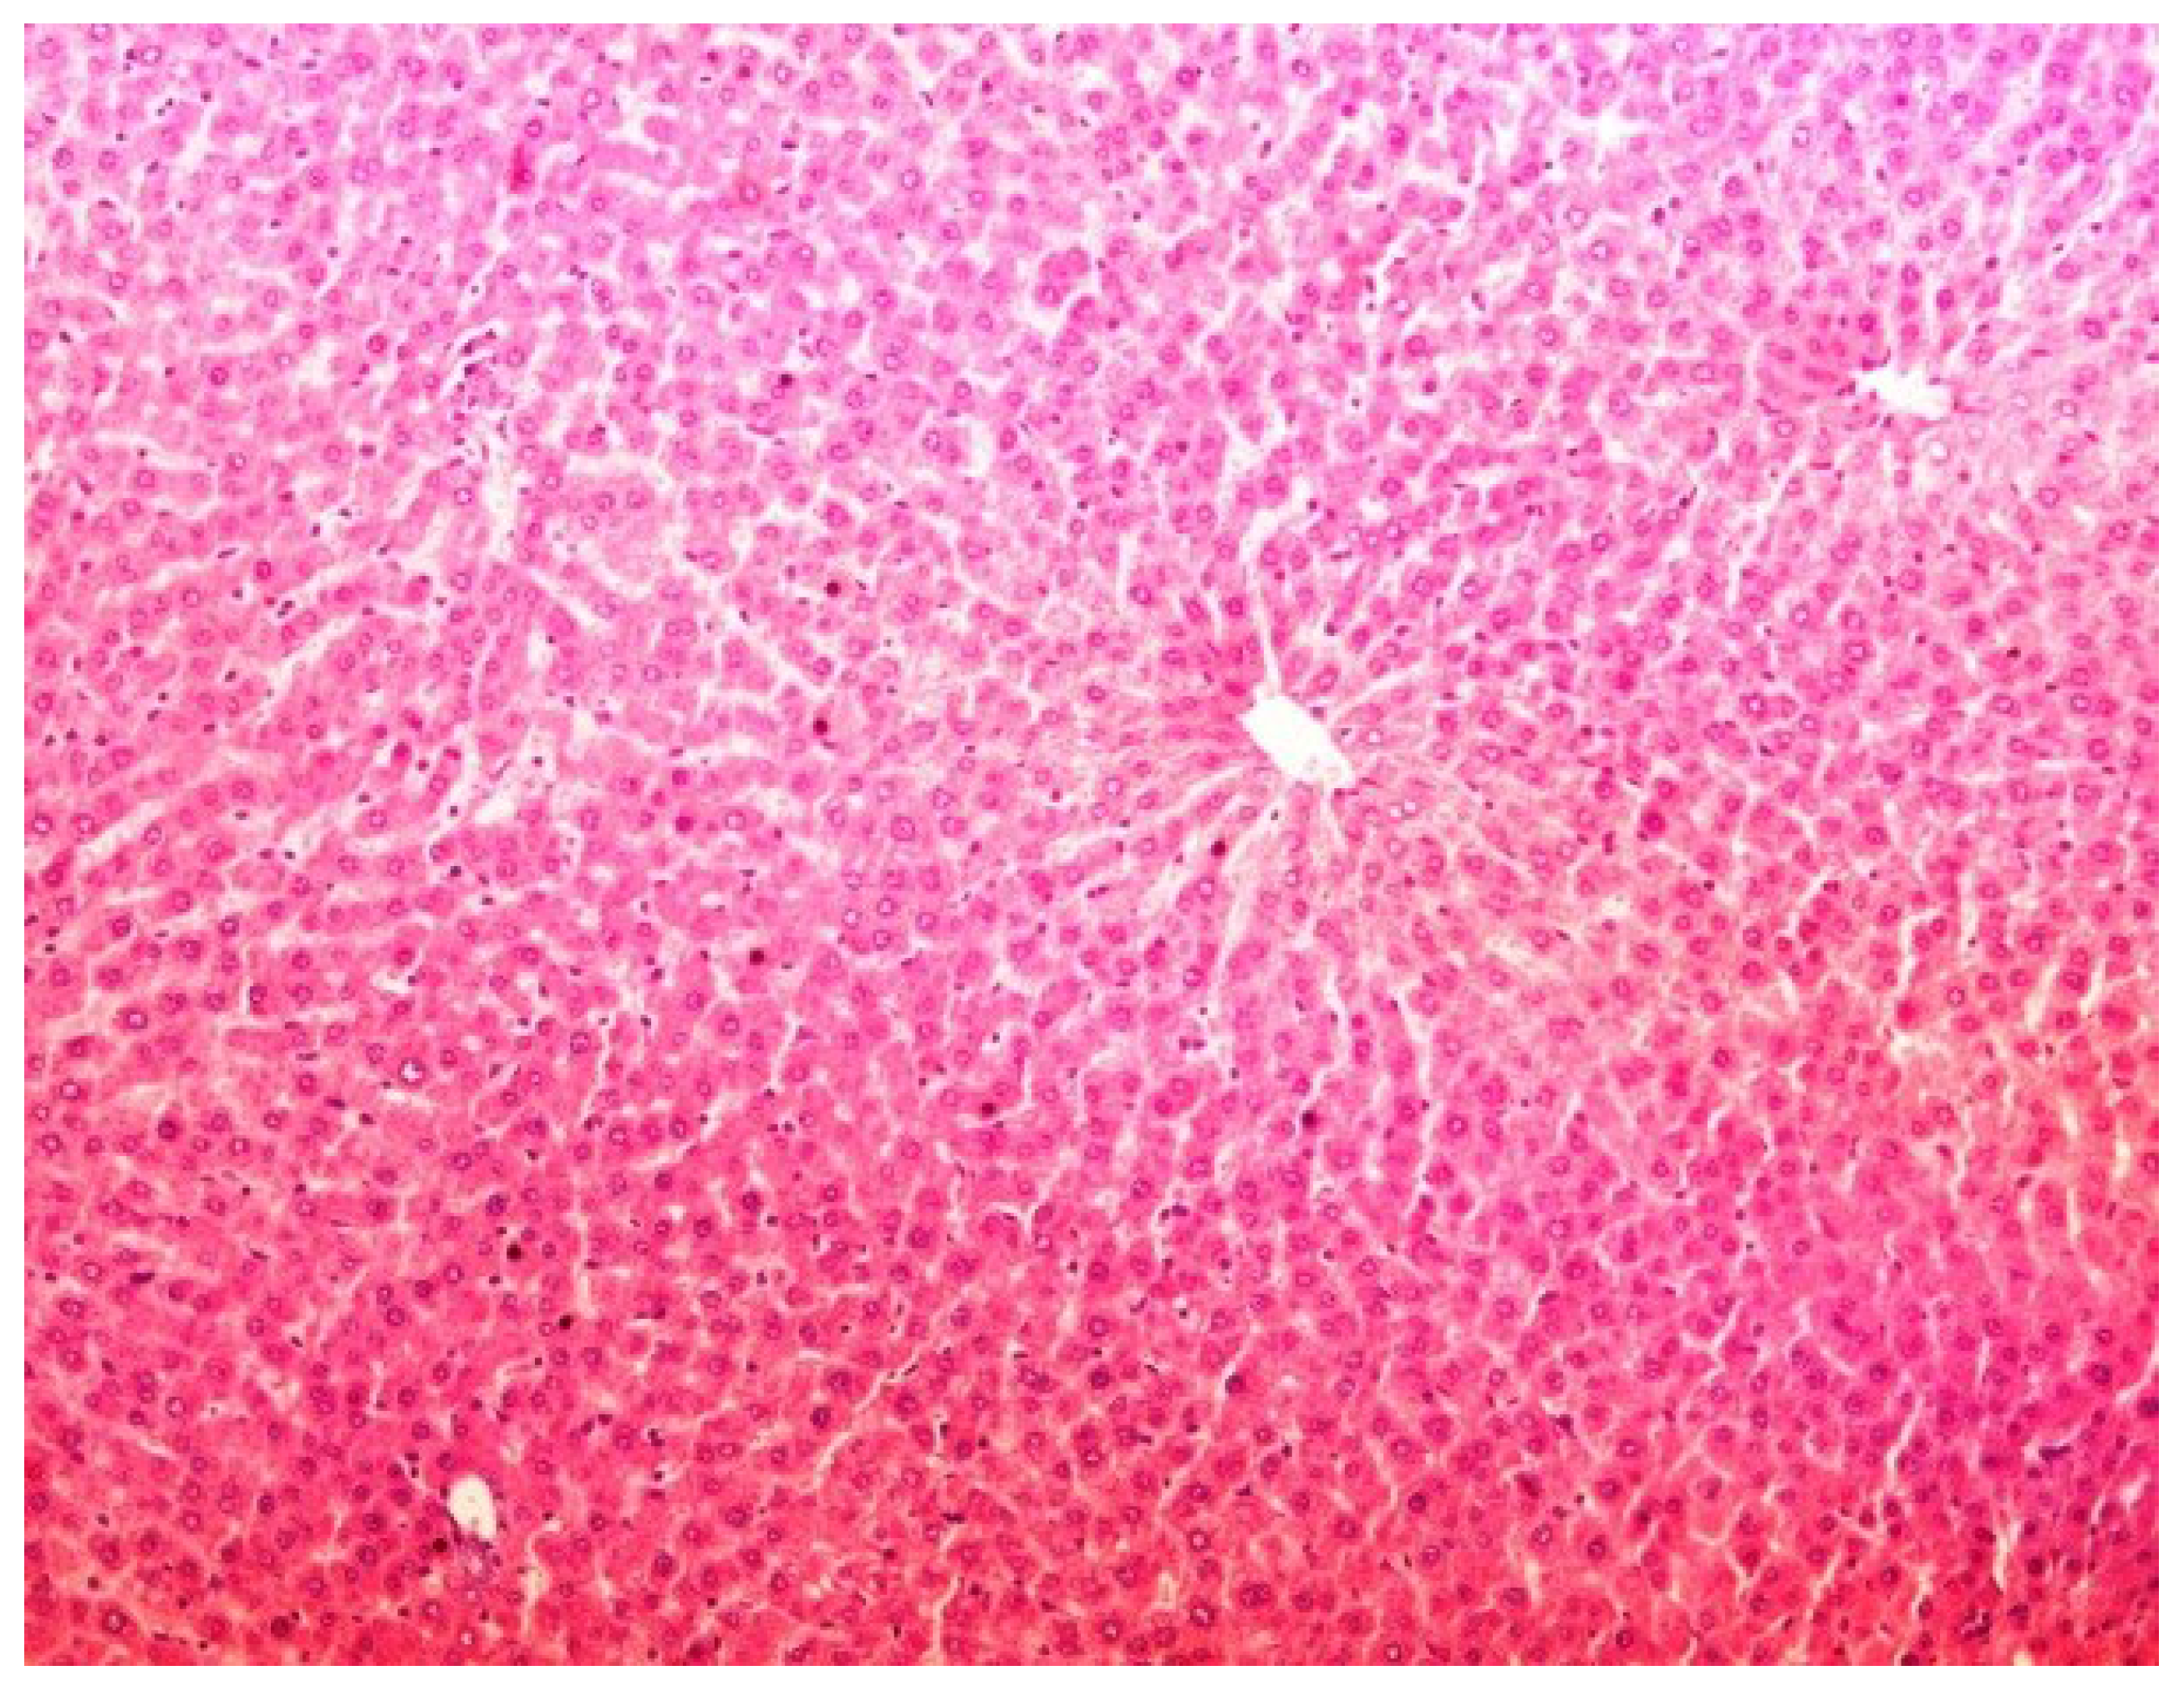

2.11. Histopathology